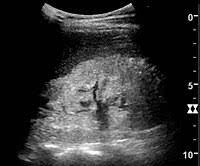

Ultrasound Appearance Of Congenital Renal Disease Pictorial Review Sciencedirect

Ultrasound Appearance Of Congenital Renal Disease Pictorial Review Sciencedirect from ars.els-cdn.com